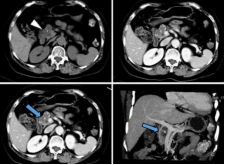

(2)腺癌CT表现:胰腺局部增大、肿块形成,多呈等或稍低密度,增强扫描多呈低密度而显示更清楚;胰头Ca常伴胰体尾萎缩;胰腺钩突变为隆凸或球形,提示钩突肿瘤;胰管和胆管扩张。

截屏2022-10-06 18.58.49

胰腺癌MRI表现:横断面所见与CT相同。T1WI肿瘤呈低或等信号,T2WI肿瘤呈稍高信号;MRCP能清晰显示梗阻扩张的胰管和胆管。

截屏2022-10-06 18.59.46